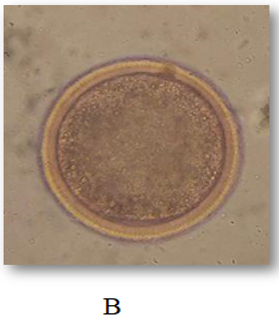

Second step, remove all non-viable oocytes, and then using the khudhory red to evaluate viability of oocytes. Then, these oocytes (viable) are left to die, by leaving them in unsuitable conditions such as low\ high temperatures or medium without nutrients outside the incubator [18], [19] [20]. Third step, again stain with khudhory red, unstained oocytes, the stain cannot inter cytoplasm are viable (live)(figure 11A), and full stain oocytes, the khudhury red pass through membrane by porous and penetrate cytoplasm (red in colour) are non-viable (dead)(figure 11B) [21], [22], [23].

Thus, it is said that every oocyte that acquires a red color is dead (non-viable), and any oocyte that does not acquire a red color is a live (vible).

Figure 11. Viable Oocyte (live) After Trypan Blue

Figure 13. Viable Oocyte (live) After Khudhory Red